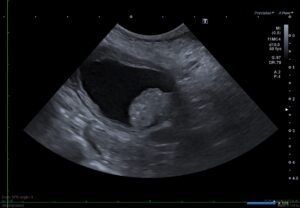

多くの場合、膀胱の出口である三角部(膀胱頸部付近)に発生するため、排尿に関わる症状が早期から現れやすい腫瘍でもあります。

膀胱三角部にできた腫瘍